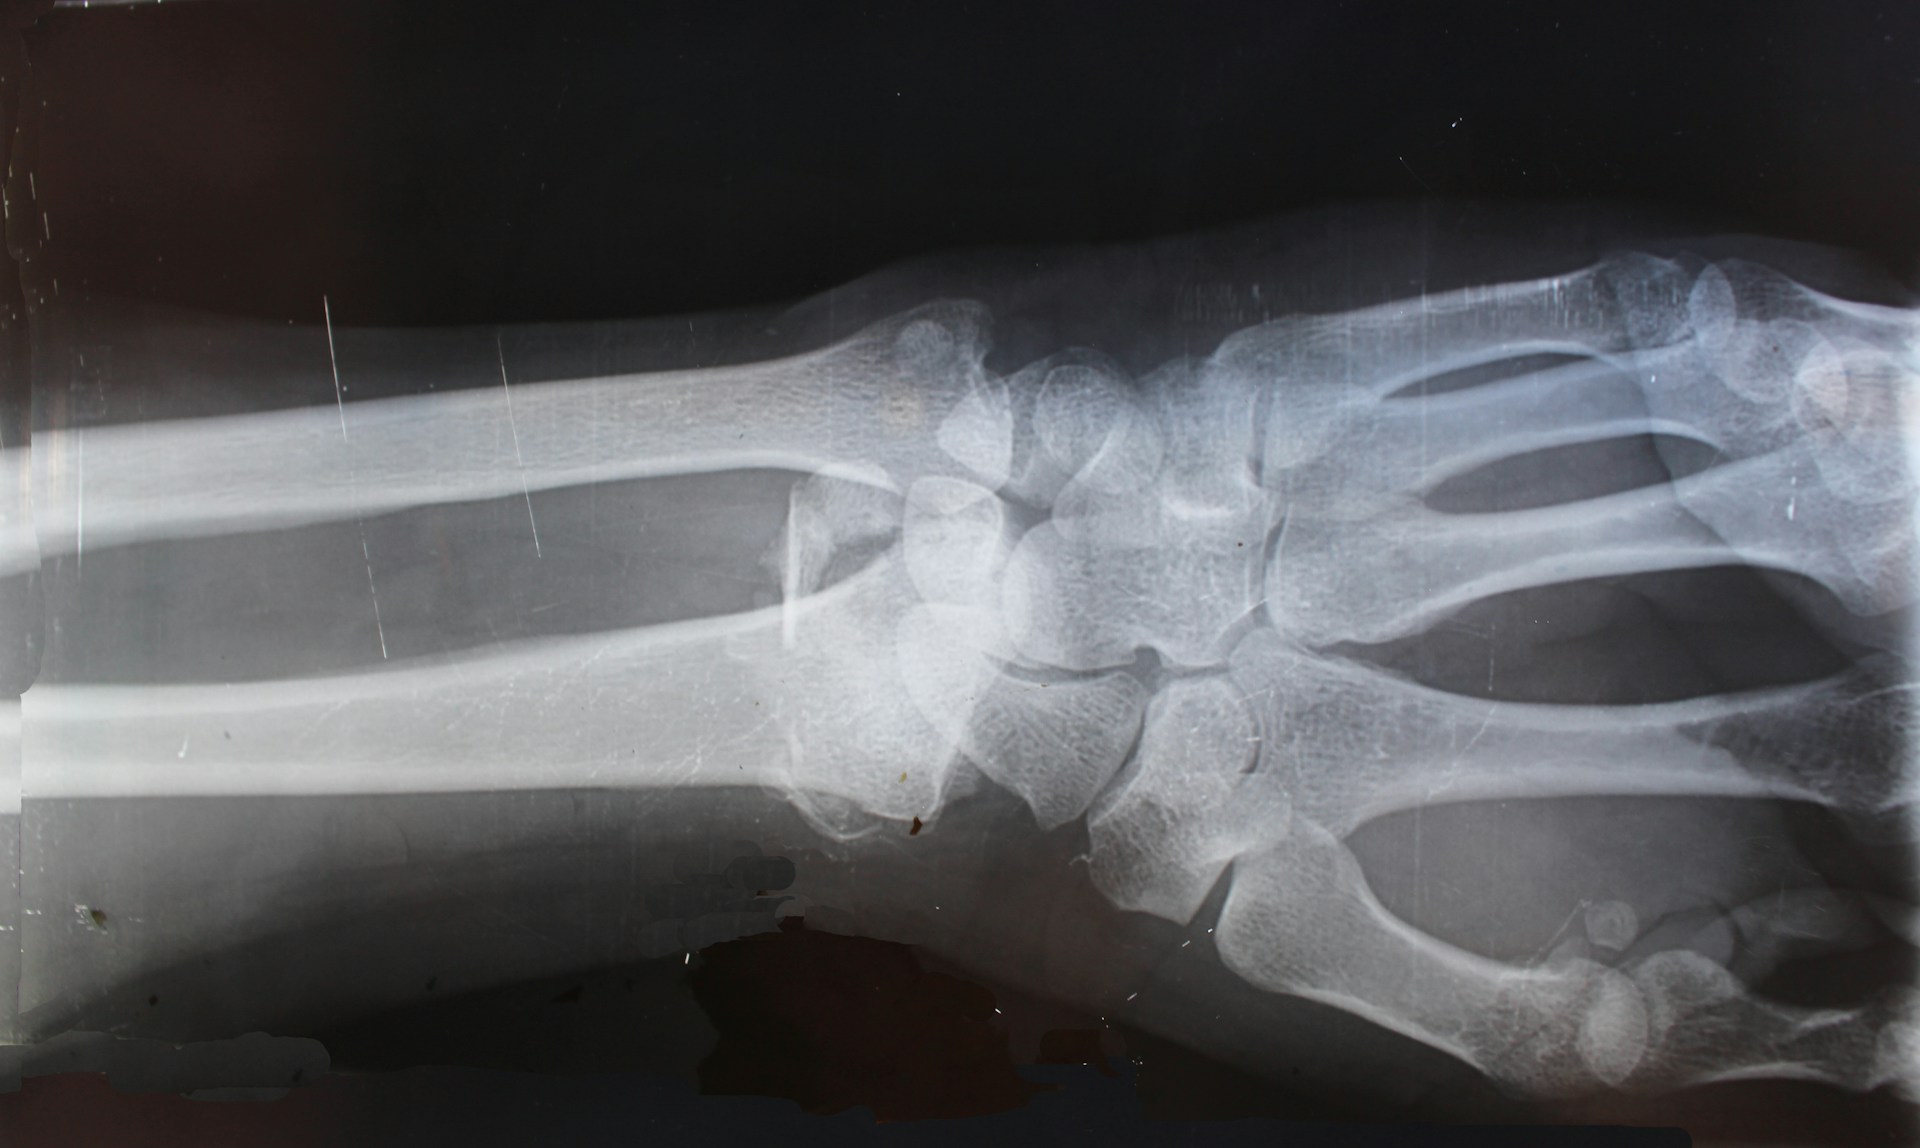

Osteogenesis Imperfecta Typu II – najcięższa postać wrodzonej łamliwości kości

Osteogenesis imperfecta (OI), znana również jako wrodzona łamliwość kości, to rzadka, genetyczna choroba tkanki łącznej, której główną cechą jest zwiększona łamliwość kości. Istnieje kilka typów tej choroby, różniących się przebiegiem klinicznym oraz rokowaniem. Typ II uznawany jest za najcięższą i zazwyczaj letalną postać tej choroby.

OI typu II najczęściej jest wynikiem mutacji w genach COL1A1 lub COL1A2, które kodują łańcuchy alfa kolagenu typu I – głównego składnika macierzy pozakomórkowej kości. Mutacje te skutkują produkcją nieprawidłowego kolagenu, co znacznie osłabia strukturę kości już na etapie życia płodowego.

OI typu II ujawnia się już w życiu płodowym i może być rozpoznana podczas badania ultrasonograficznego w ciąży. Do charakterystycznych objawów należą:

- Liczne złamania kości już in utero

- Deformacje kości długich, szczególnie kończyn dolnych

- Niewykształcone lub skrócone żebra

- Hipoplazja płuc (niedorozwój płuc) prowadząca do ciężkiej niewydolności oddechowej

- Mała masa urodzeniowa

- Czaszka miękka, łatwo podatna na ucisk

Diagnostyka

Rozpoznanie można postawić na podstawie:

- USG prenatalnego – wykazującego złamania i deformacje kości

- RTG noworodka – ujawnia liczne złamania i zniekształcenia szkieletu

- Badania molekularne – potwierdzające obecność mutacji w genach kolagenu

Odmiany typu II

Typ II sam w sobie dzieli się na podtypy (IIA, IIB, IIC), różniące się wyglądem szkieletu w badaniach obrazowych. To pokazuje, jak złożona i różnorodna może być nawet jedna „kategoria” choroby.

Osteogenesis imperfecta typu II to dramatyczna i najcięższa postać wrodzonej łamliwości kości. Charakteryzuje się letalnym przebiegiem i znacznymi deformacjami układu kostnego już w okresie prenatalnym. Chociaż współczesna medycyna umożliwia wczesne rozpoznanie choroby, wciąż pozostaje ona nieuleczalna. Z tego względu kluczowe znaczenie ma opieka nad rodziną oraz zapewnienie godnych warunków życia dla dziecka przez ten krótki czas.